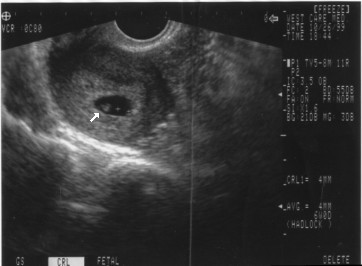

Here I am at 5 weeks 5 days